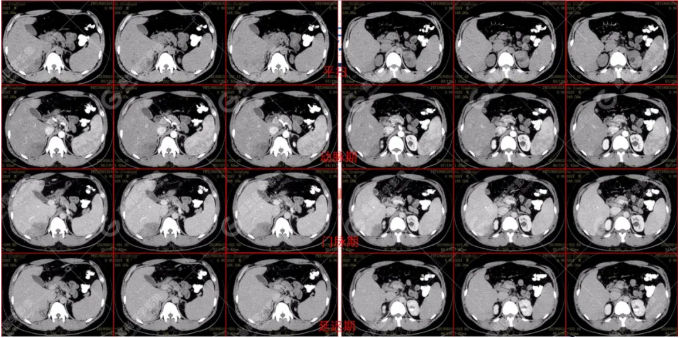

B超及CT檢查發(fā)現(xiàn):肝臟多發(fā)低密度占位。

PET/CT全身圖

PET/CT診斷

嗜酸性粒細(xì)胞增多癥肝浸潤(rùn)

根據(jù)骨髓穿刺及抗寄生蟲(chóng)治療后好轉(zhuǎn)情況,最終確診為嗜酸性粒細(xì)胞增多癥肝浸潤(rùn)(肝寄生蟲(chóng)病所致)

吡喹酮治療前兩天體溫驟然升高,之后體溫恢復(fù)正常,半個(gè)月后CT復(fù)查肝臟病變體積較前明顯縮小、吸收。